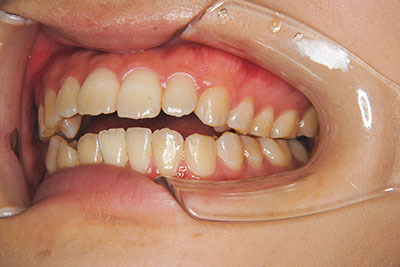

おとなの方でも矯正治療をあきらめないでください!

いくら歯が動き易くとも、本人がやる気でなければ効果は出ませんし、むし歯発生のリスクも高まります。おとなの方は顎の成長が終わっているため、治療の計画が立てやすいとも言えます。「もう大人だから…」とあきらめず、一度ご相談ください。